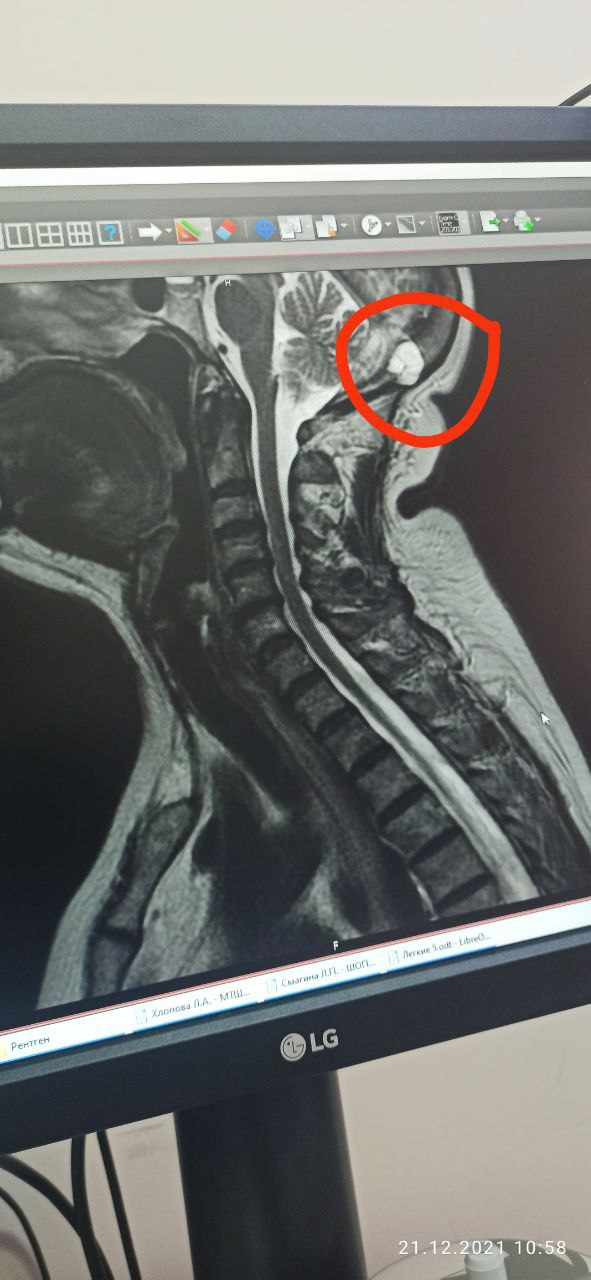

Issayev Assan in Radiology/Рентгенология Чат

Здравствуйте. Как называется такая штука?